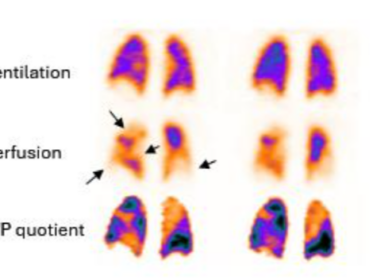

La medicina nucleare polmonare ha attraversato una fase di profonda trasformazione scientifica e tecnologica, consolidando il ruolo della scintigrafia di ventilazione e perfusione (V/Q) non solo come strumento diagnostico per l’embolia polmonare, ma come metodica fondamentale per lo studio funzionale dell’apparato respiratorio. L’evoluzione dai protocolli planari alle acquisizioni tomografiche (SPECT) e l’integrazione della tomografia computerizzata…